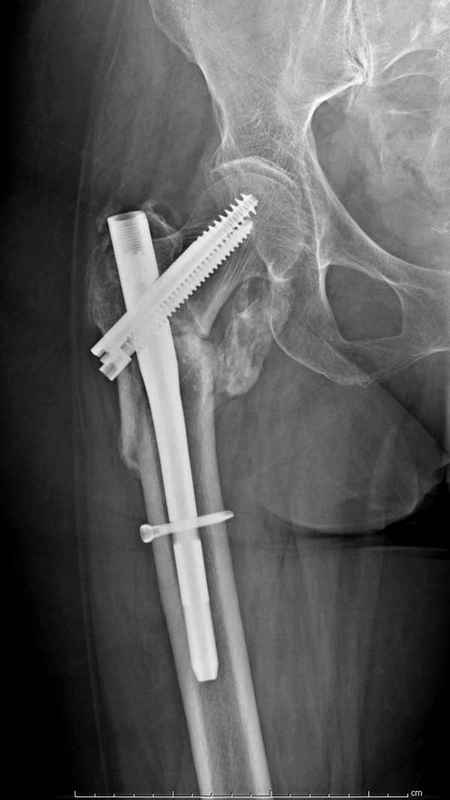

Здесь 83 года, травма в результате падения

Из фиксаторов, мы бы применили цефаломедуллярные, потому что они "по закону моментов" из-за короткого рычага от центра головки к диафизу и по принципу "головка диафиз" механически лучше выдерживают нагрузки, чем пластины.

Но современные пластины с угловой стабильностью не отстают от медуллярных конструкций. Межфрагментарные шурупы и имплант как нейтрализирующее создаст адекватную фиксацию.

судя по картинкам с ЭОПа явно использовались приемы непрямой репозиции под его контролем, а так же интраоперационный ЭОП-контроль положения винтов, без такого контроля операция может ухудшить ситуацию (опять же учтите сроки) т.к. результат буде зависеть в большей степени от искусства хирурга, а не от технологии